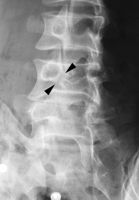

scotty dog sign은 spine oblique 에서만 볼 수 있다. 보통 척추전방전위증(spondylolisthesis)를 진단하는데 활용된다.

scotty dog sign이 있는 사진들이다. 이 정도는 되야 개 한마리 봤다고 할 수 있다.